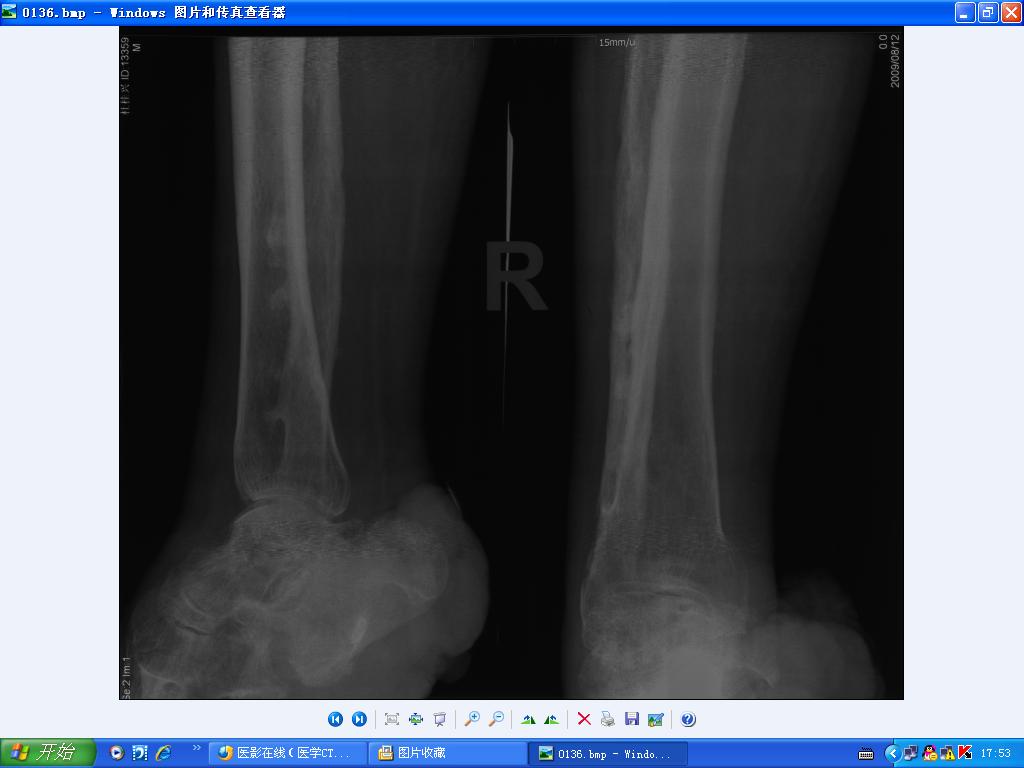

老年男性,麻风病患者已治愈,左下肢议肢,现发现右足踝部较大溃疡半年余,恶臭,专科检查见右足踝部有一菜花样肿物,触之易出血,病理高分化鳞癌。全身体格检查尚可。请教肿瘤和麻风病的关系?菜花样肿物

1、麻风病骨改变。2、软组织皮肤鳞状细胞癌。

1、麻风病骨改变。2、踝部软组织皮肤鳞状细胞癌,与慢性溃疡经久不愈及感染有关。

1、麻风病骨改变。2、踝部软组织皮肤鳞状细胞癌,与慢性溃疡经久不愈及感染有关。两者没有关系